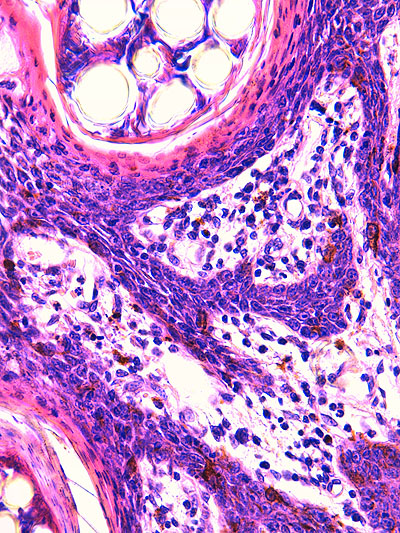

Photo 2 (Hémalun Eosine X 40) : au faible grossissement, l’épiderme revêt un aspect bleu-blanc-rouge,

bleu pour hyperplasie des couches basales, blanc pour vacuolisation des acanthocytes sous-cornés et

rouge pour parakératose de la couche cornée. Le derme est faiblement à modérément inflammatoire.

Légendes de la Photo 2 :

- Flèche bleue : hyperplasie des couches basales

- Flèche blanche : vacuolisation des acanthocytes sous-cornés

- Flèche rouge : pour parakératose de la couche cornée

- Étoile rouge : Le derme est faiblement à modérément inflammatoire